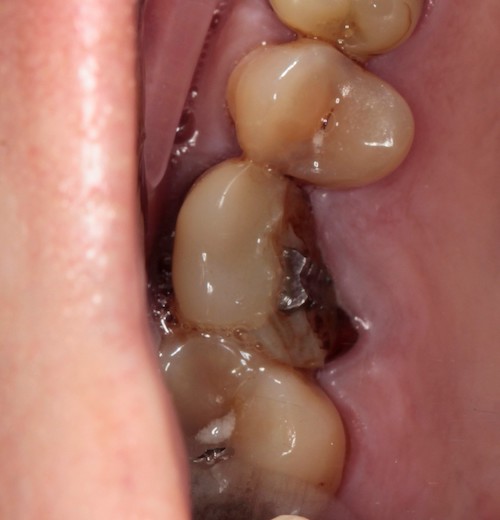

Природа не терпит пустоты. Именно поэтому если продолжительное время не заниматься восстановлением потерянного зуба, рядом стоящие начнут наклоняться в сторону дефекта.

Рис.6 Зубы рядом с дефектом наклонены.Нет места для протезирования

А также выдвигаться верхний зуб, которому больше не с чем контактировать.